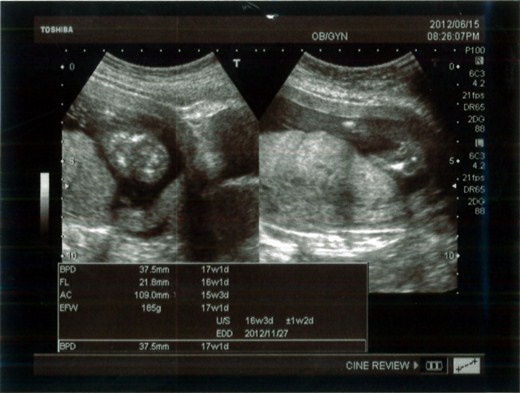

[孕事2] 16W‧性別判定、唐氏症篩檢

16周的產檢

生產檢結果出來,小龍包是個龍包妹

►這胎肚子大的很快,才16w就已經94cm,跟之前懷小兔比時,六個月一樣大! 哈

►小兔比已經1Y4M了,可是還是很怕生喔,帶他一起去產檢,就會大哭,即使檢查的是媽媽,她可能以為是她要打預防針吧! 倒是醫生很逗趣的想要安撫她看電視 (超音波妹妹的動態) 不過他還是不領情~~哇哇哭的!